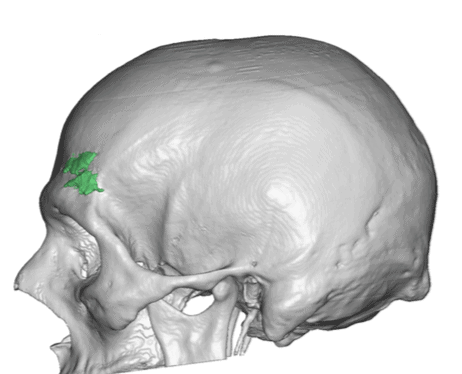

Patient 110

Desire for head shape asymmetry improvement as the final stage of total skull reshaping surgeries. (previous skull implants are in green color)

Placement of custom temporal implant through an incision behind the ear.

Desire for head shape asymmetry improvement as the final stage of total skull reshaping surgeries. (previous skull implants are in green color)

Placement of custom temporal implant through an incision behind the ear.